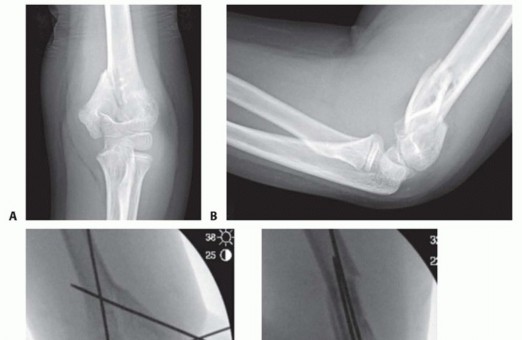

FIG 1 • A,B. An 8-year-old boy with T-condylar distal humerus fracture. C,D. Fixed with mini-open reduction with intercondylar screw compression and K-wire fixation of the distal humerus to the shaft. E,F. After hardware removal, the patient had 0 to 140 degrees range of motion with no pain.

In younger children, an acceptable result can often be obtained with closed reduction and pinning, although this is generally not as straightforward as in a standard supracondylar humerus fracture (FIG 1).